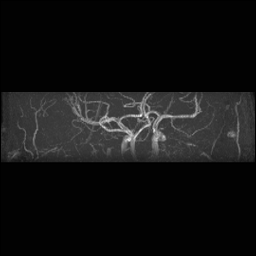

Circle of Willis, projections

For Circle of Willis projection images:

View #3